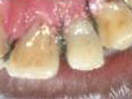

Dead discolored tooth

with a growth in bone

The Smile after placing

the Temporary Crown.